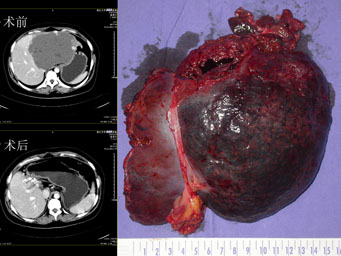

腹腔镜技术在肝胆胰脾外科的临床研究及应用 蔡秀军 彭淑牖 虞 洪 梁 霄 王先法&n...